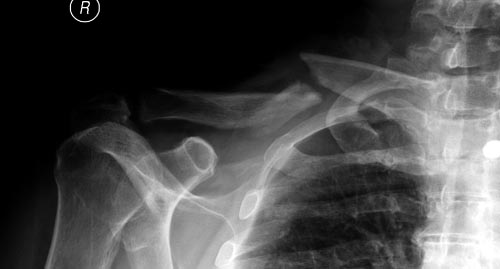

Уважаемые коллеги. Обратился пациент 29лет, оперирован в 2007 г. в Республиканском центре по поводу перелома ключицы и/м спицей, после несращения повторно оперирован в 2008 году, со слов больного освежение и повторно фиксация спицами, и обратился только через 6 лет, активные и пассивные движения в правом плечевом суставе в полном объеме, беспокоит только слабость при поднятии тяжести и подвижность в с/з ключицы. Р-снимок прилагается.Честно признаться, пока не знаю, что делать, имеются обычные пластины из ЦИТО, спицы, может, краевая резекция до появления «росы» дефект заполнить спонгиозной костью, фиксация и/м двумя спицами, загнуть оба конца спицы с компрессей, или пластина…или вообще не трогать. Прощу не критиковать, имеем то, что имеем, пациент в НИИТО не может ехать из-за финансов. С уважением Абдурашид.

Оставлять так однозначно нельзя. Сам по себе ложный сустав не срастется. По поводу спиц думаю, что если с двух попыток не решили проблему, не решат и в третий раз, так как не обеспечивают стабильный остеосинтез.

Краевая резекция до появления "росы", заполнить дефект аутокостью, стабилизировать отломки пластиной с у/с максимально атравматичным способом. На мой взгляд оптимальное решение.